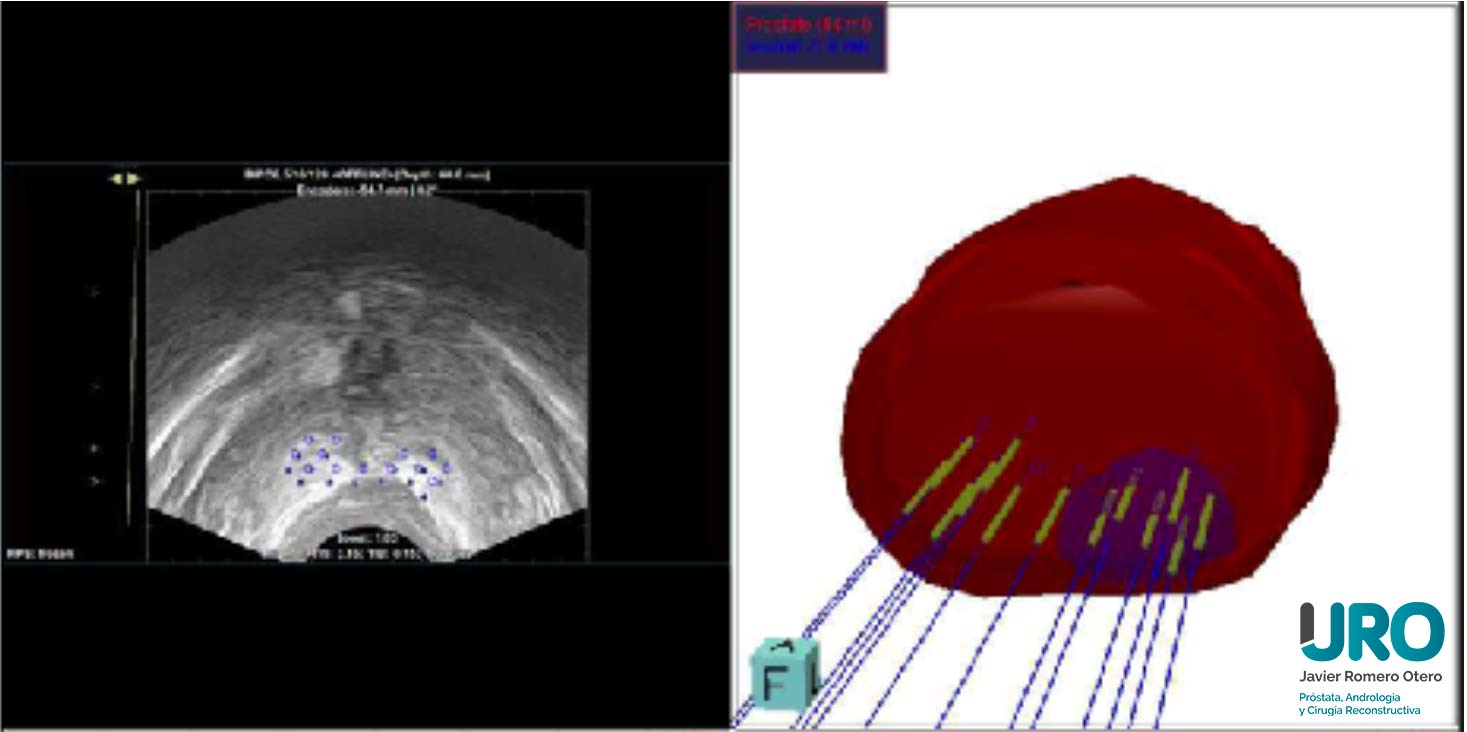

En España se diagnostican al año más de 34.000 casos de cáncer de próstata. El abanico de opciones terapéuticas es amplio, disponiendo de tratamientos mínimamente invasivos como la terapia focal para tratar únicamente el área tumoral.

La terapia focal como tratamiento para el cáncer de próstata es una de las opciones terapéuticas mínimamente invasivas con la que se consiguen los mismos resultados oncológicos que con otras terapias, pero con mínimas secuelas funcionales.